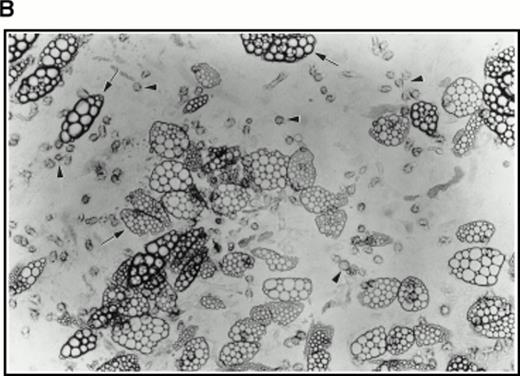

Very few cells survived this procedure. Indeed, as assayed by Trypan blue staining of a small sample, all visible cells were found to be nonviable. However, when used to initiate long-term cultures on preformed, irradiated stroma, this population of cells proved very active in establishing hematopoiesis as evidenced by extensive lipid deposition and characteristic “cobblestone” areas (Fig 4B).

Aspirated bone marrow cells were separated on Ficoll and the mononuclear cell fraction isolated. These cells were then incubated for 7 days in medium supplemented with soluble human SCF, IL-3, and 5-FU. A sample of cells from a such a culture at 4 days of incubation is shown in Fig 4A (top right panel), together with a control culture in which the 5-FU was omitted (Fig 4A, top left panel), by way of comparison. A strikingly different picture was observed in the presence of 5-FU with the majority of the surviving cells being terminally differentiated cells such as erythrocytes and polymorphs. Large cells with expanded nuclei and prominent cytoplasm frequent in the untreated cultures were conspicuous by their absence. To show that the cells surviving the 5-FU treatment were quiescent, 24 hours before harvesting, tritiated thymidine was added to the cultures to label any dividing cells. After 7 days of culture in the selective medium, the cells were collected onto microscope slides by Cytospin and dipped in autoradigraphic emulsion. Prominent clusters of silver grains could be seen in untreated control cultures (Fig 4A, middle left panel), whereas cells from the 5-FU–treated culture were unlabeled (Fig 4A, middle right panel). The cells were also analyzed for high-level expression of the SCF receptor, a marker for the 5-FU–resistant cells.3 As shown in Fig 4A, the 5-FU–resistant cells (bottom right panel) all showed bright fluorescence with a FITC-conjugated anti-SCF receptor antibody, whereas the untreated controls (bottom left panel) showed a wide spectrum of intensities, confirming that 5-FU selects a subset of cells with a higher level of expression of SCF receptor.

(A) Selection of quiescent bone marrow cells using 5-FU. Bone marrow mononuclear cells were incubated for 7 days in IMDM either supplemented with IL-3, SCF, and 5-FU to kill dividing cells (right-hand panels) or not (left-hand panels). At 4 days of incubation an aliquot was spun onto microscope slides and stained with Wright’s stain (top panels). Twenty-four hours before harvesting, 3H thymidine was added to the cultures. Following 7 days incubation cells were obtained and spun onto microscope slides. The slides were dipped in photographic emulsion and exposed for 7days before being developed, counterstained with Wright’s stain, and visualized under the light microscope (middle panels). (Bottom panels) Cells as above, but stained with antibody to c-kit and viewed under fluorescence. (B) Long-term culture. 5-FU–selected cells were plated on monolayers of bone marrow derived fibroblast as described in Materials and Methods and used to initiate long-term bone marrow cultures. The arrows show areas of extensive lipid deposition characteristic of these types of culture. Arrowheads identify “cobblestone areas,” clusters of developing hematopoietic cells.